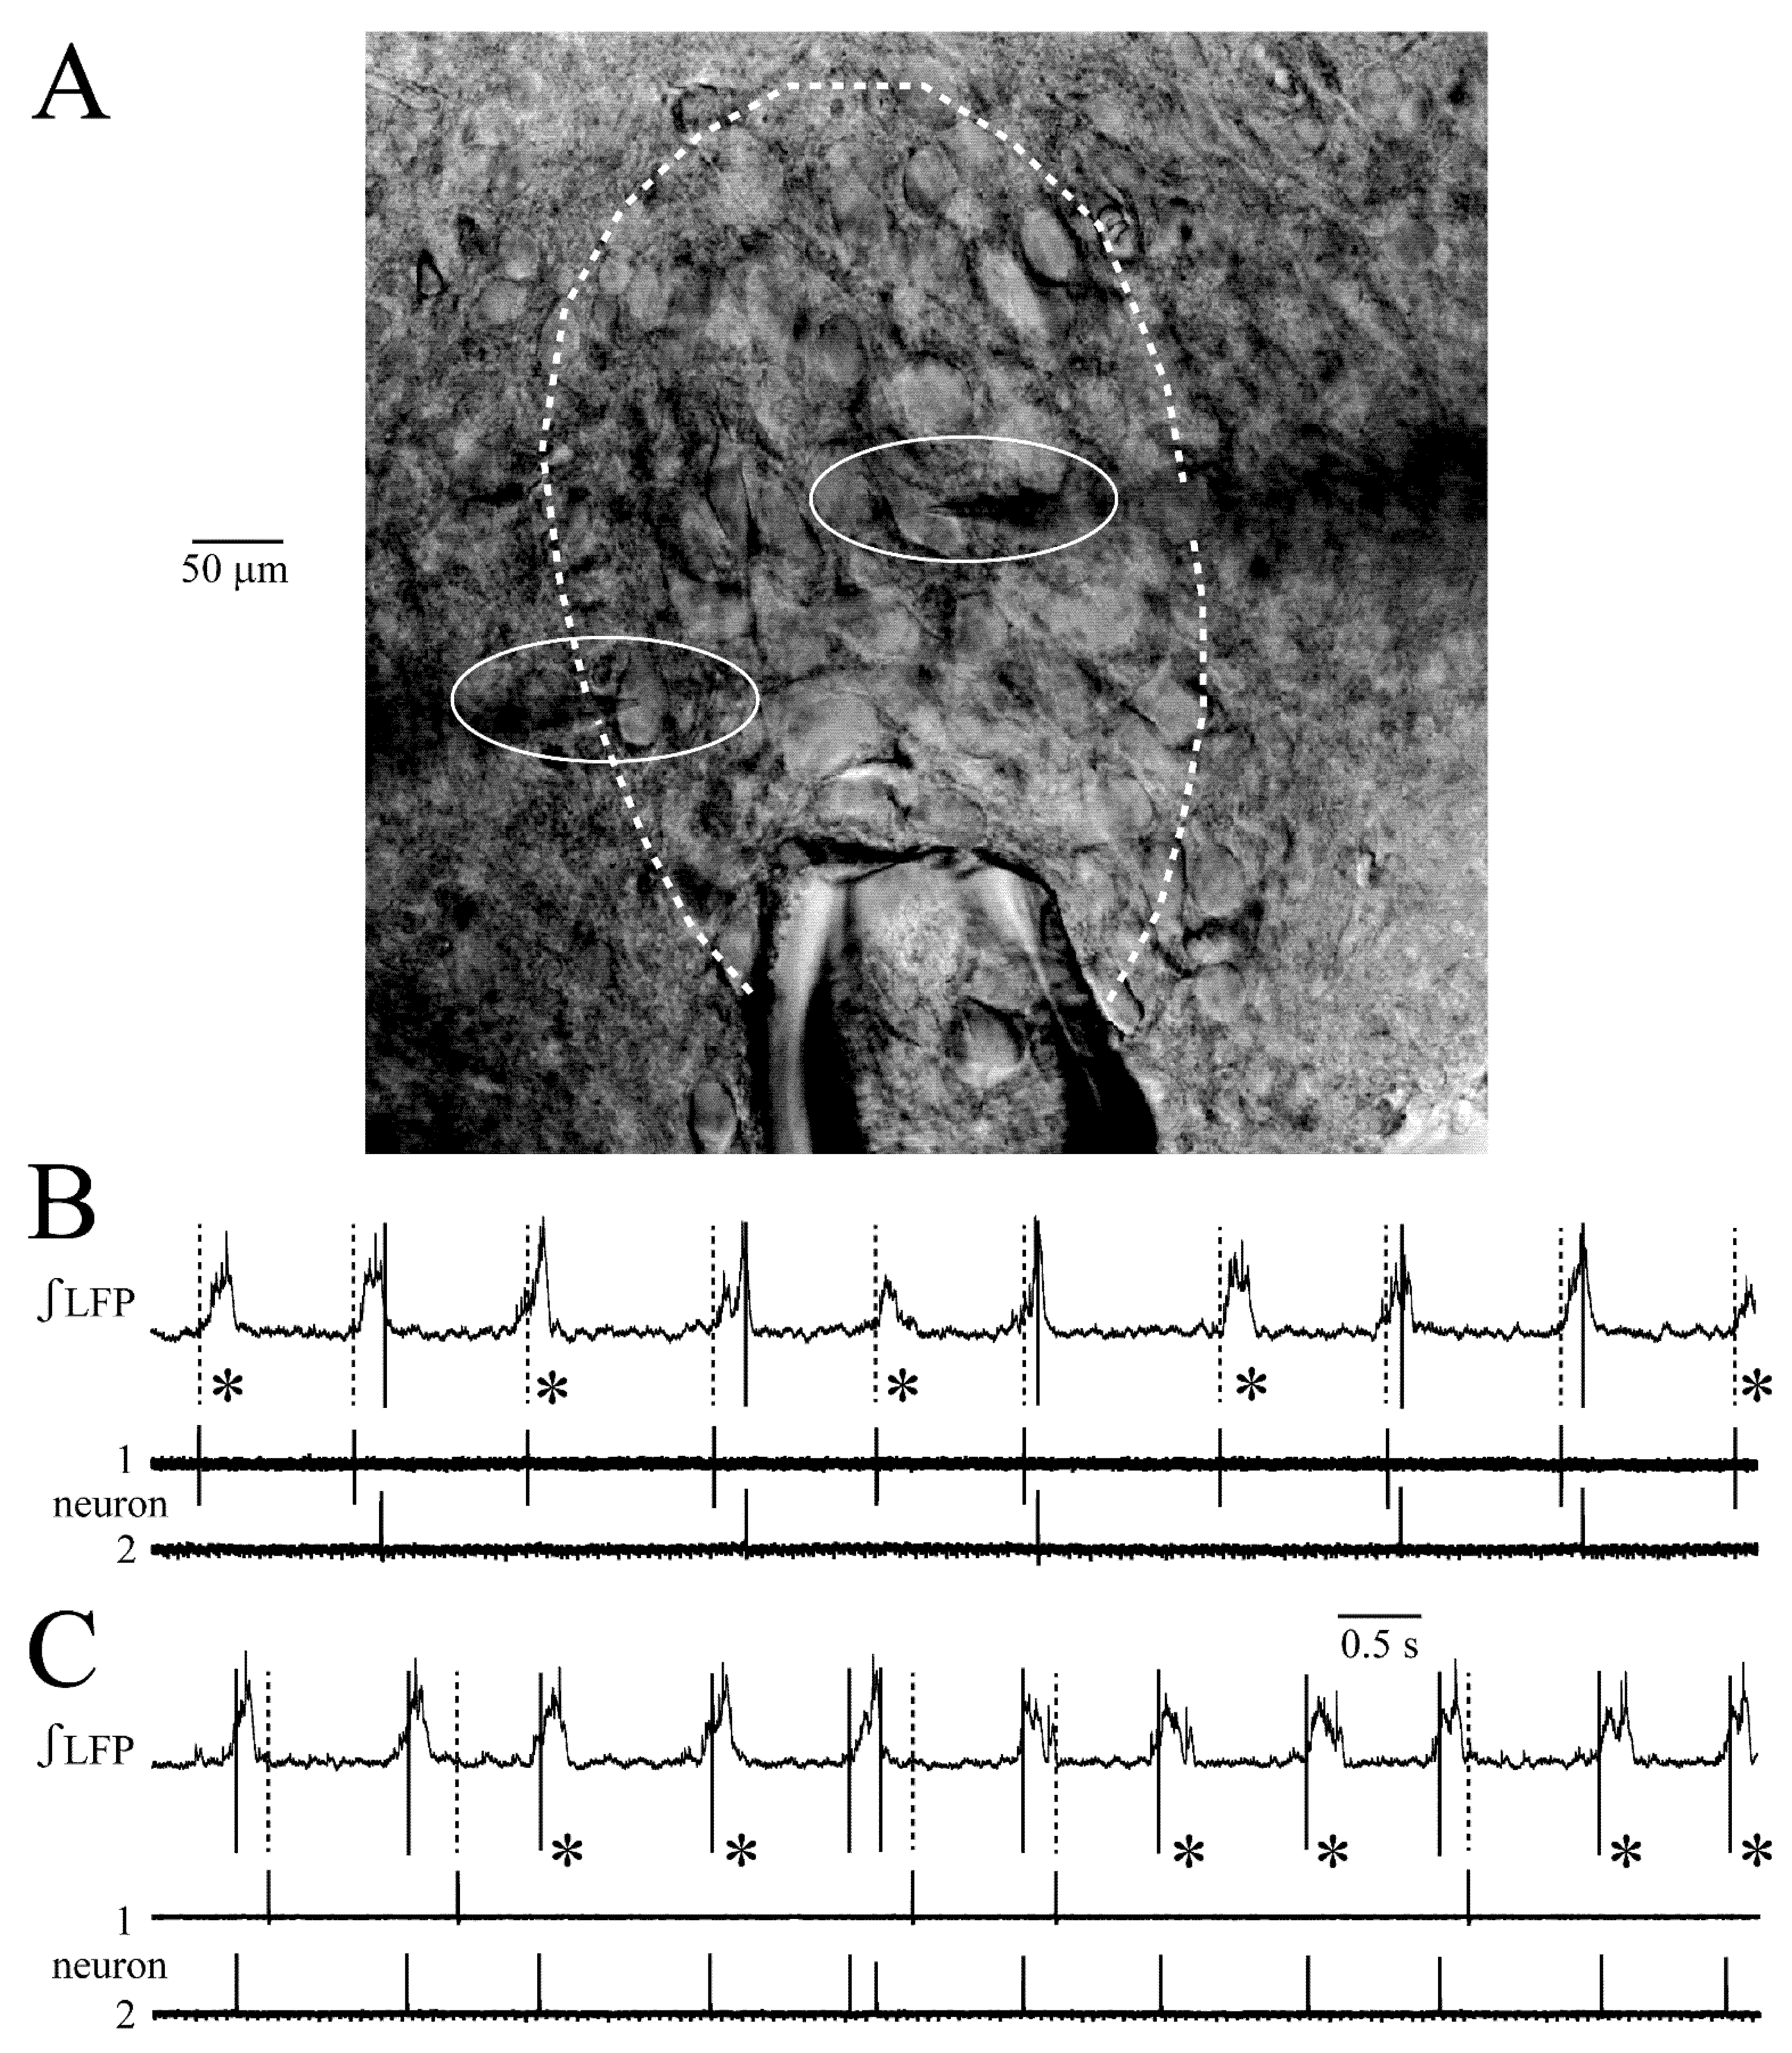

3.1. LFP Shape and Signal Analysis

3.7. Persistence of Single Neuron Spiking during Network Inhibition

4.1. LFP Recording of LC Discharge Pattern Transformation

4.2. LC Synchrony Analysis with Combined LFP and Single Neuron Recording